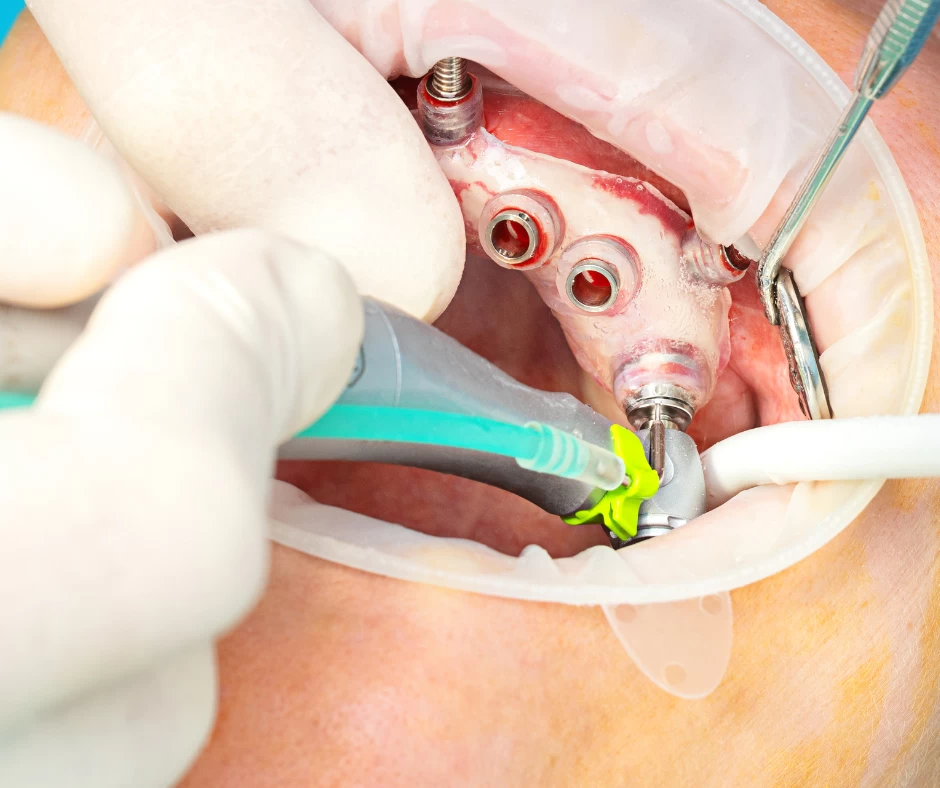

مراحل کاشت ایمپلنت دندان در ونک، ایمپلنت دندان یکی از پیشرفتهترین روشهای جایگزینی دندانهای از دست...

ایمپلنت دندان یکی از روشهای مطمئن و پرکاربرد در جایگزینی دندانهای از دسترفته است. موفقیت این جراحی...

عوارض احتمالی و ریسکهای مرتبط با پیوند استخوان در جراحی ایمپلنت در ونک. امروزه کاشت ایمپلنت دندان به...

انواع روش های پیوند استخوان و مزایا و معایب هر کدام در کاشت ایمپلنت دندان در ونک. بازسازی استخوان یکی...